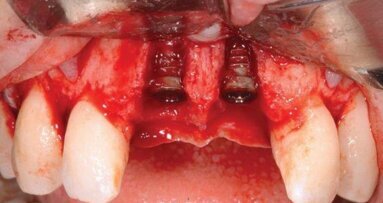

Leczenie endodontyczne przeprowadzono metodą step-back. Kanały wypełniano metodą kondensacji bocznej gutaperki, jako uszczelniacz stosowano pastę AH26 (Dentsply). W celu odbudowy braku zęba stosowano implanty SPI firmy Alpha Bio. Są to implanty charakteryzujące się jedną z wyższych stabilizacji pierwotnych wśród systemów implantologicznych. Kształt nadający właściwości samonawiercające umożliwia zmianę pozycji w trakcie wprowadzania i ukierunkowanie implantu.

Po przeprowadzeniu leczenia implantologicznego i endodontycznego oceniano parametry kliniczne wokół zębów leczonych endodontycznie i implantów. W celu tej oceny stosowano zmodyfikowany na potrzeby badania indeks PES (Tab.1). Badanie kliniczne obejmowało ocenę estetyki tkanek miękkich oraz głębokości kieszonek przyzębnych zęba leczonego endodontycznie oraz implantu. Pomiary przeprowadzano bezpośrednio po zacementowaniu pracy długoczasowej na implancie, tzn. po 6 miesiącach od jego wprowadzenia. W tym samym czasie przeprowadzano badanie kliniczne zębów leczonych endodontycznie. Kolejny raz ocenę kliniczną przeprowadzano po 12 miesiącach od rozpoczęcia leczenia.

Autor prezentuje przypadek ekstrakcji z wczesną implantacją i jednoczasowym przeszczepem kości i tkanek miękkich.